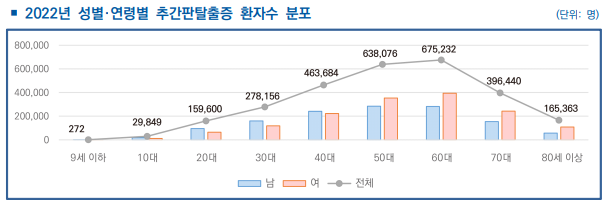

오늘은 척추 질환 중에서 대표적인 추간판탈출증(디스크)의 정의와 증상, 진단 그리고 재활 운동 방법에 대해서 안내드리도록 하겠습니다. 추간판탈출증은 우리가 흔히 알고 있는 디스크라고 불리는 척추 질환 중 하나입니다. 추간판탈출증의 환자수를 살펴보면, 2022년 약 270만여 명(대한민국 전체 인구의 약 5%)으로 나타났으며, 60대 여성의 발병률이 가장 높았습니다. 당뇨병이 약 15% 정도인 것을 보았을 때, 추간판탈출증이 흔하게 발생하고 있음을 알 수 있습니다.